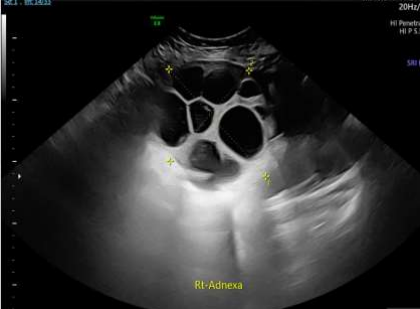

The patient was admitted under the care of the gynaecology team and provided with pain relief and hydration. A pelvic ultrasound was scheduled, but the extreme pain precluded a transvaginal examination. A transabdominal ultrasound revealed bilateral enlarged ovaries with multiple cysts of varying sizes, mild internal vascularity, and the following dimensions: right ovary 12 × 12 × 10 cm and left ovary 23 × 18 × 9 cm. Moderate free fluid was detected within the pouch of Douglas, with a depth of 10.7 cm. The appearance of ovaries corresponded with ovarian hyperstimulation syndrome.

Figure 2